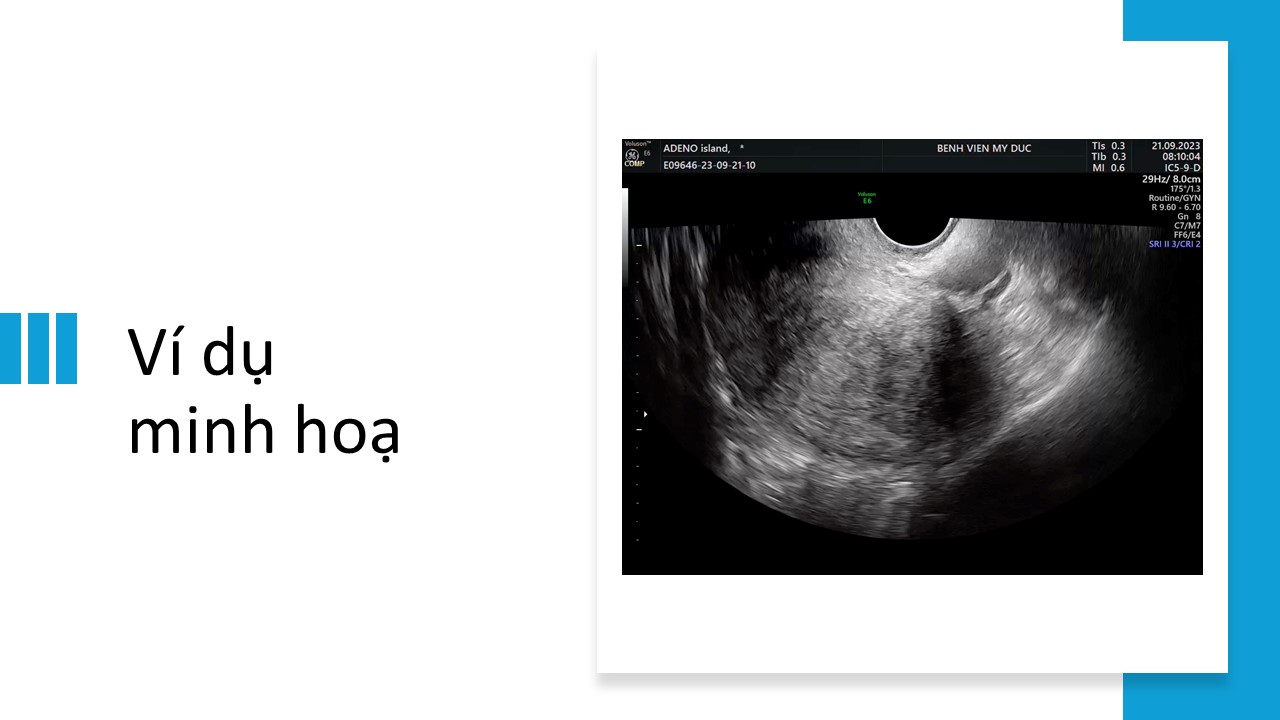

Siêu âm đánh giá adenomyosis theo đồng thuận MUSA

Từ khóa: Siêu âm đánh giá adenomyosis theo đồng thuận MUSA